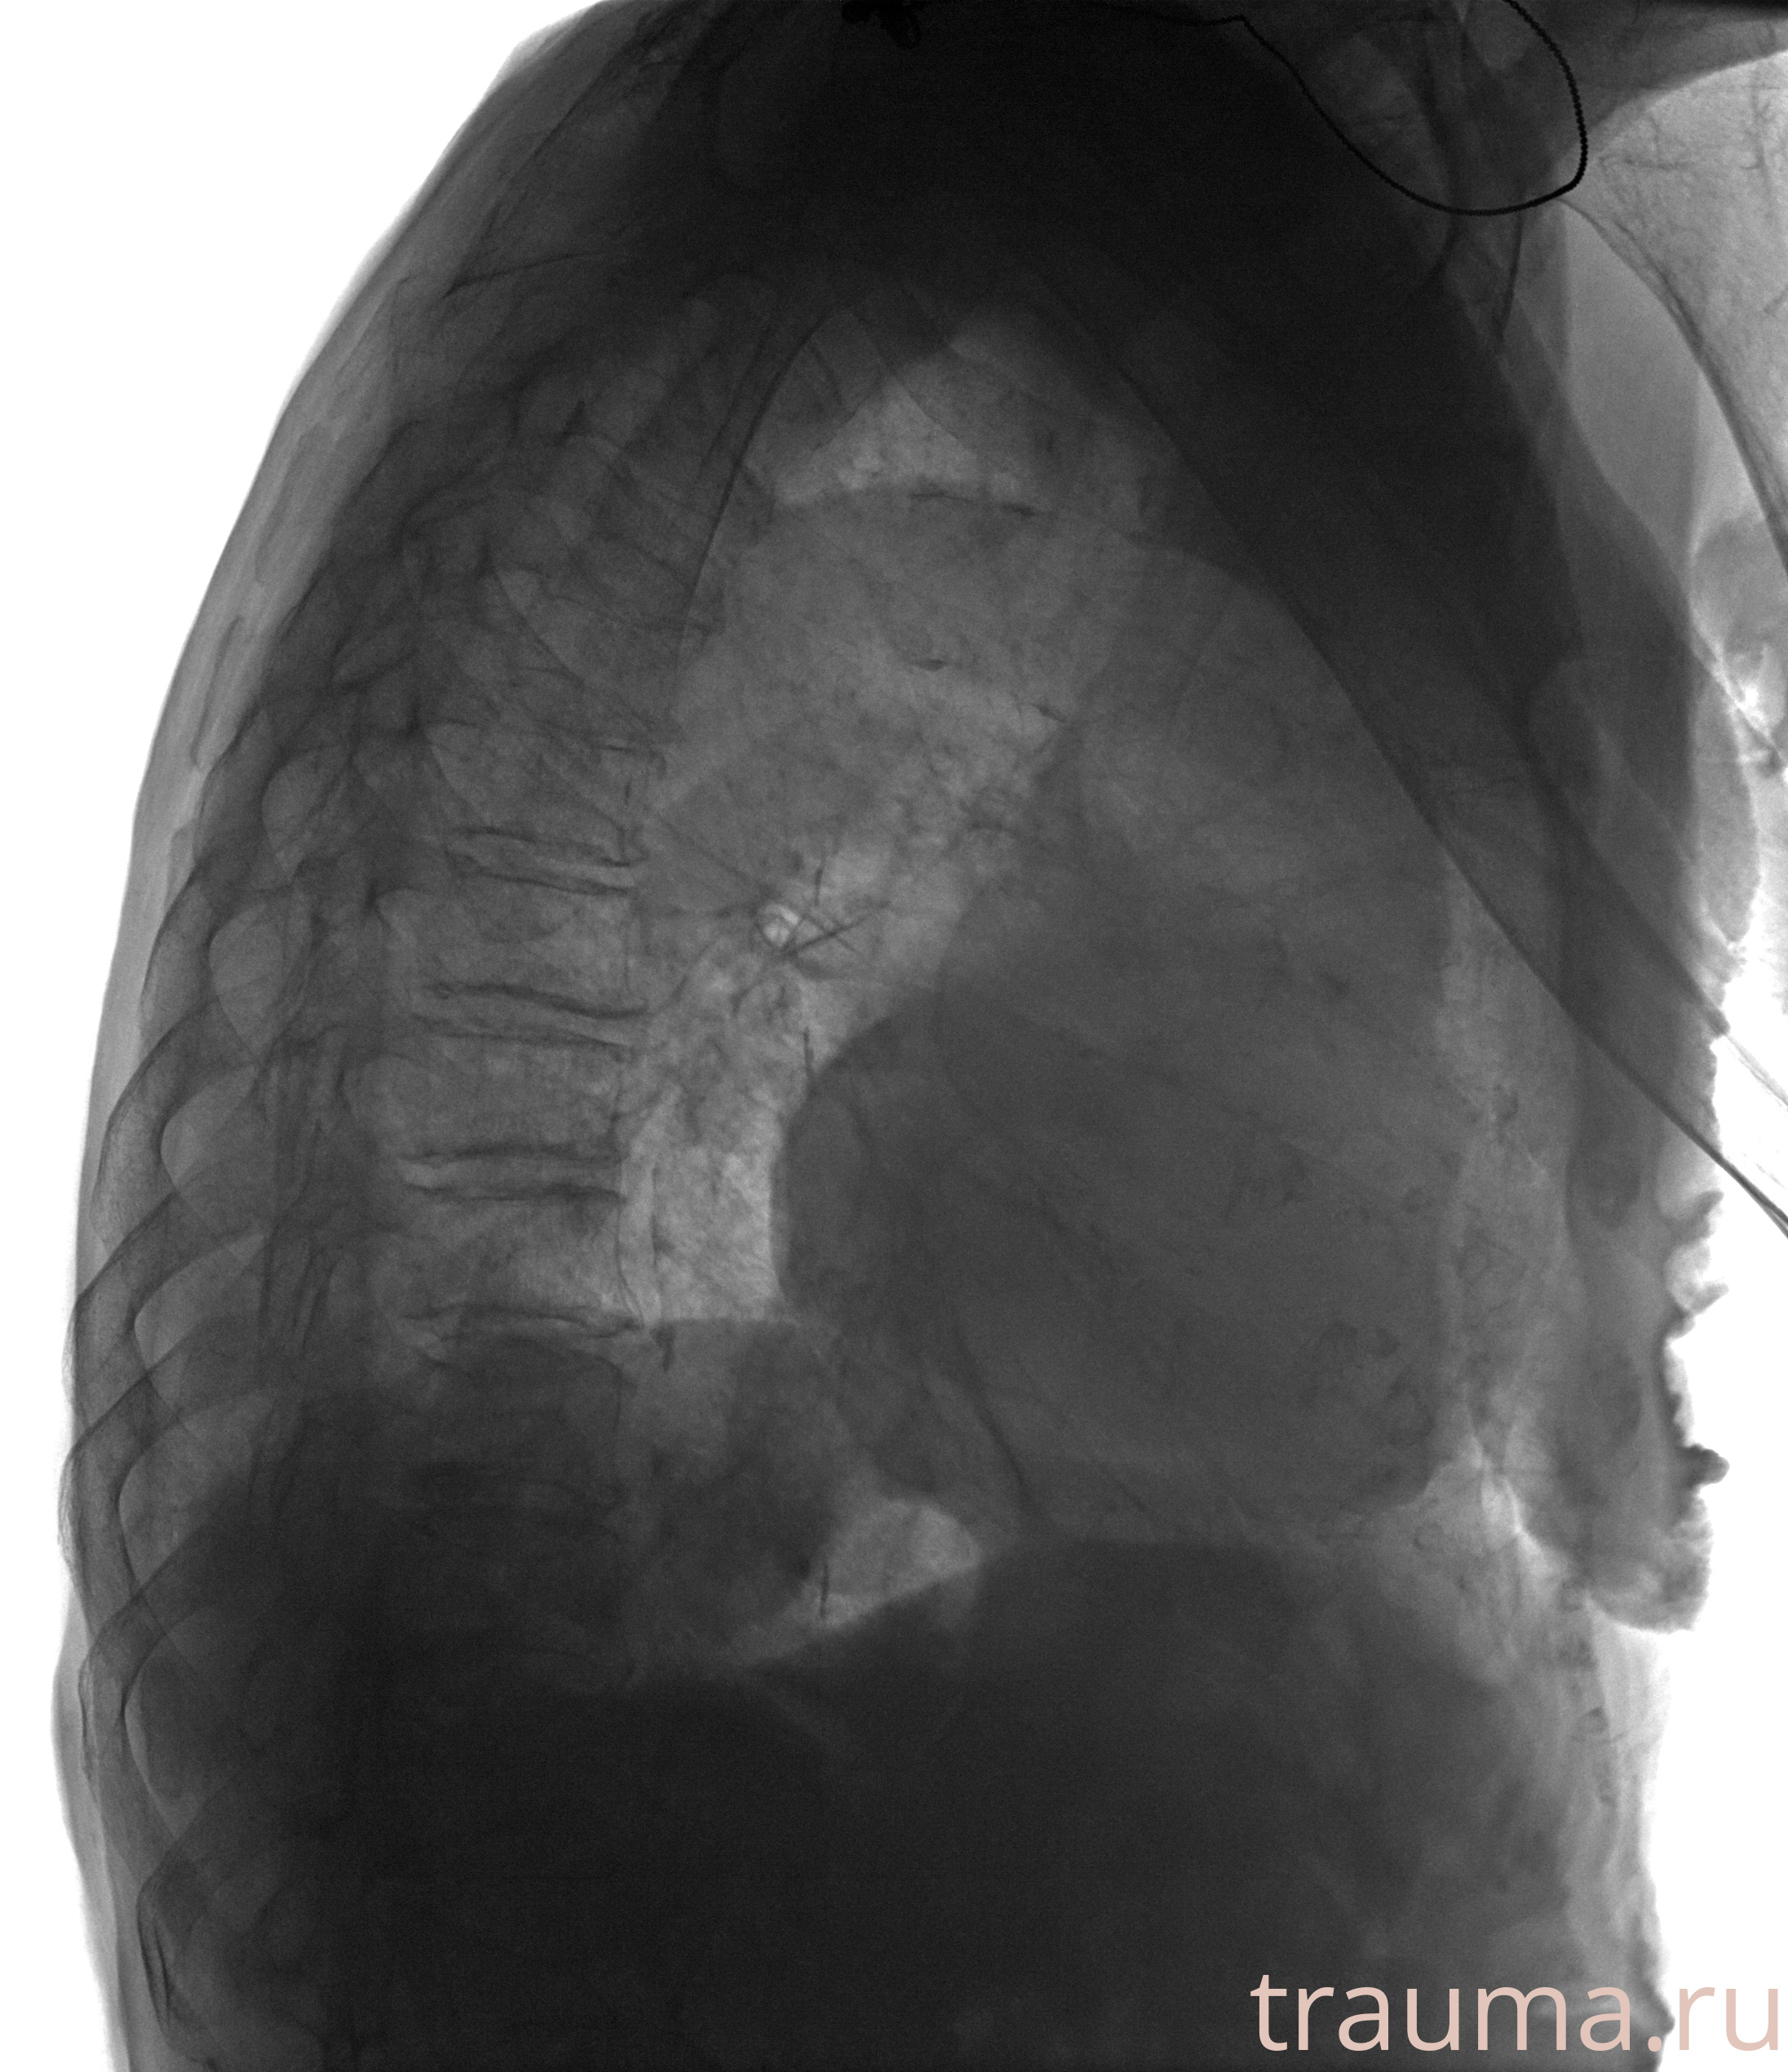

Рентгенограммы

Рентген на дому: по вашему адресу приезжает врач-рентгенолог, травматолог-ортопед с мобильным рентгеновским аппаратом, проводит диагностику травмы или заболевания, делает необходимые рентгенограммы, дает рекомендации по дальнейшему лечению. Получить качественные снимки в домашних условиях возможно благодаря уникальной методике, разработанной МосРентген Центром для института  Склифосовского